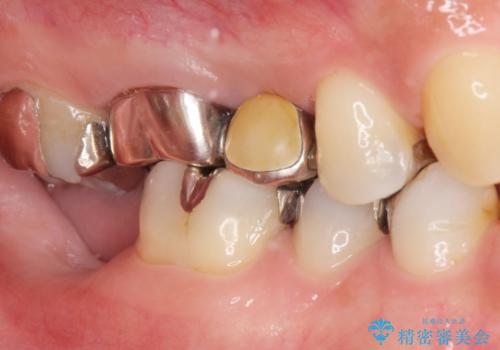

患者様のご希望によりPGA(金白金合金)クラウンによる補綴を行いました。

インプラントの種類:アルファタイト

クラウンの種類:PGA(Platinum Gold cast Alloy・金白金合金)クラウン